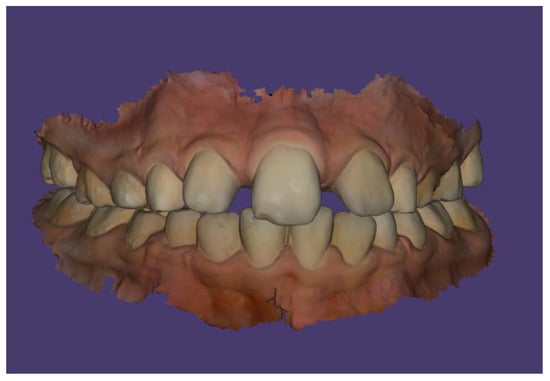

Case Description